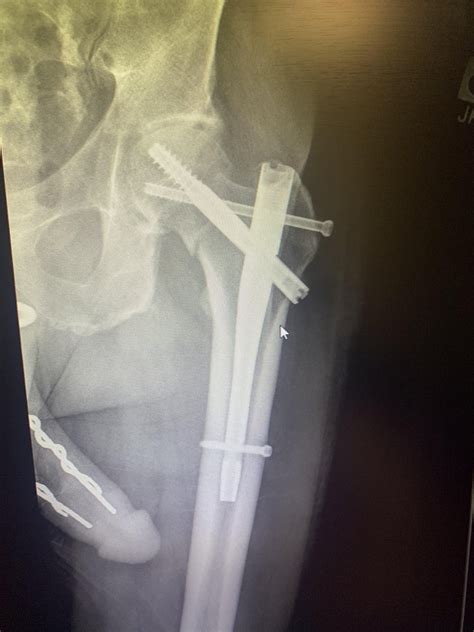

• Imaging Studies: Imaging studies, such as MRI, CT scans, and X-rays, provide valuable insights into a patient's health status. Clinical correlation helps radiologists and other healthcare providers interpret these images more accurately by comparing them with other clinical data.